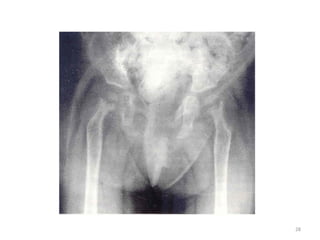

4- BASSIN – RACHIS

- Aplatissement du bassin

- Coxa vara

LESIONS DIAPHYSAIRES

- Diminution de la densité osseuse

- Amincissement des corticales

- Aspect de corticale feuilletée

- Coxa vara, genu varum

- Pseudo-fracture de Looser- Milkmann